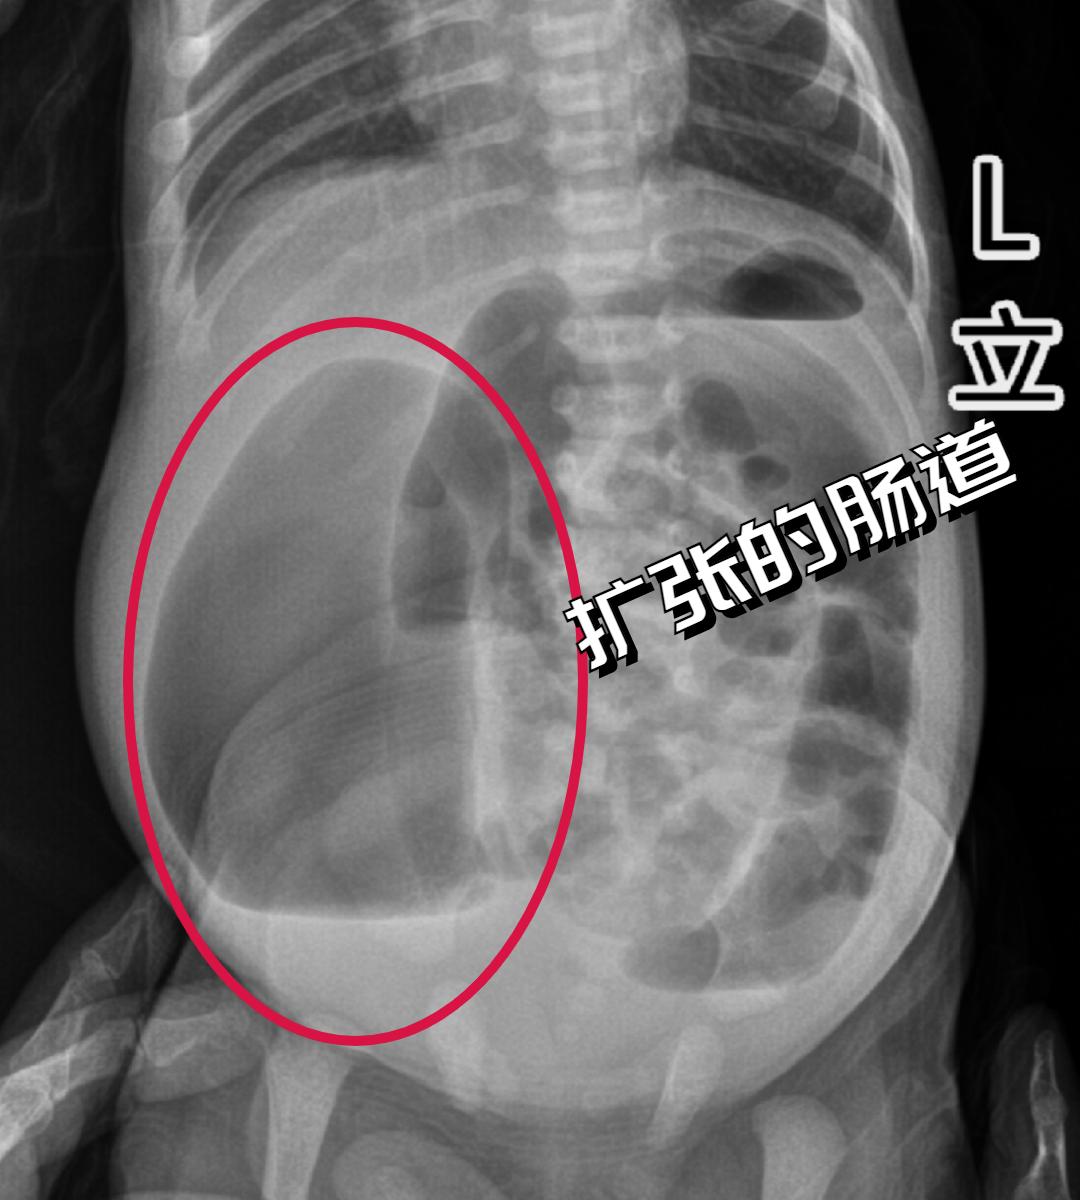

面对小宝凶险万分的病情,对小儿外科疑难危重病人的诊治、抢救有着丰富经验的周小渔教授当机立断,尝试从小宝的瘘口插管进行减压。随着小宝肠道内的气体和其他内容物从管道排出,再结合检查结果,周小渔教授松了一口气: 小宝不需要进行风险更高的急诊手术了,可以安心待到术前检查完善后再择期手术。